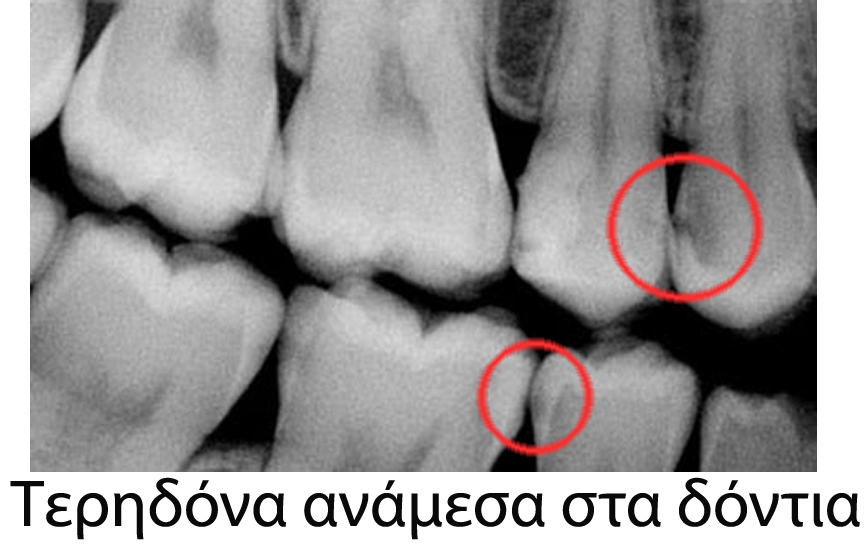

Εμείς προλαβαίνουμε τις μεγάλες τερηδόνες, τα βαθιά σφραγίσματα και τις επακόλουθες ενδοδοντικές θεραπείες (απονευρώσεις), με τον τακτικό έλεγχο στο ιατρείο όπου εκτός των άλλων μεθόδων διάγνωσης, κάνουμε λήψη ειδικών ακτινογραφιών που μας επιτρέπει να δούμε αν υπάρχει τερηδόνα στα σημεία επαφής των δοντιών (ανάμεσα στα δόντια), περιοχές που δεν φαίνονται με το μάτι, ούτε από τον ασθενή, ούτε από τον οδοντίατρο. Μάλιστα, αν διαγνώσουμε την τερηδόνα σε πολύ αρχικό στάδιο, είναι εφικτό το να γλιτώσουμε το σφράγισμα!